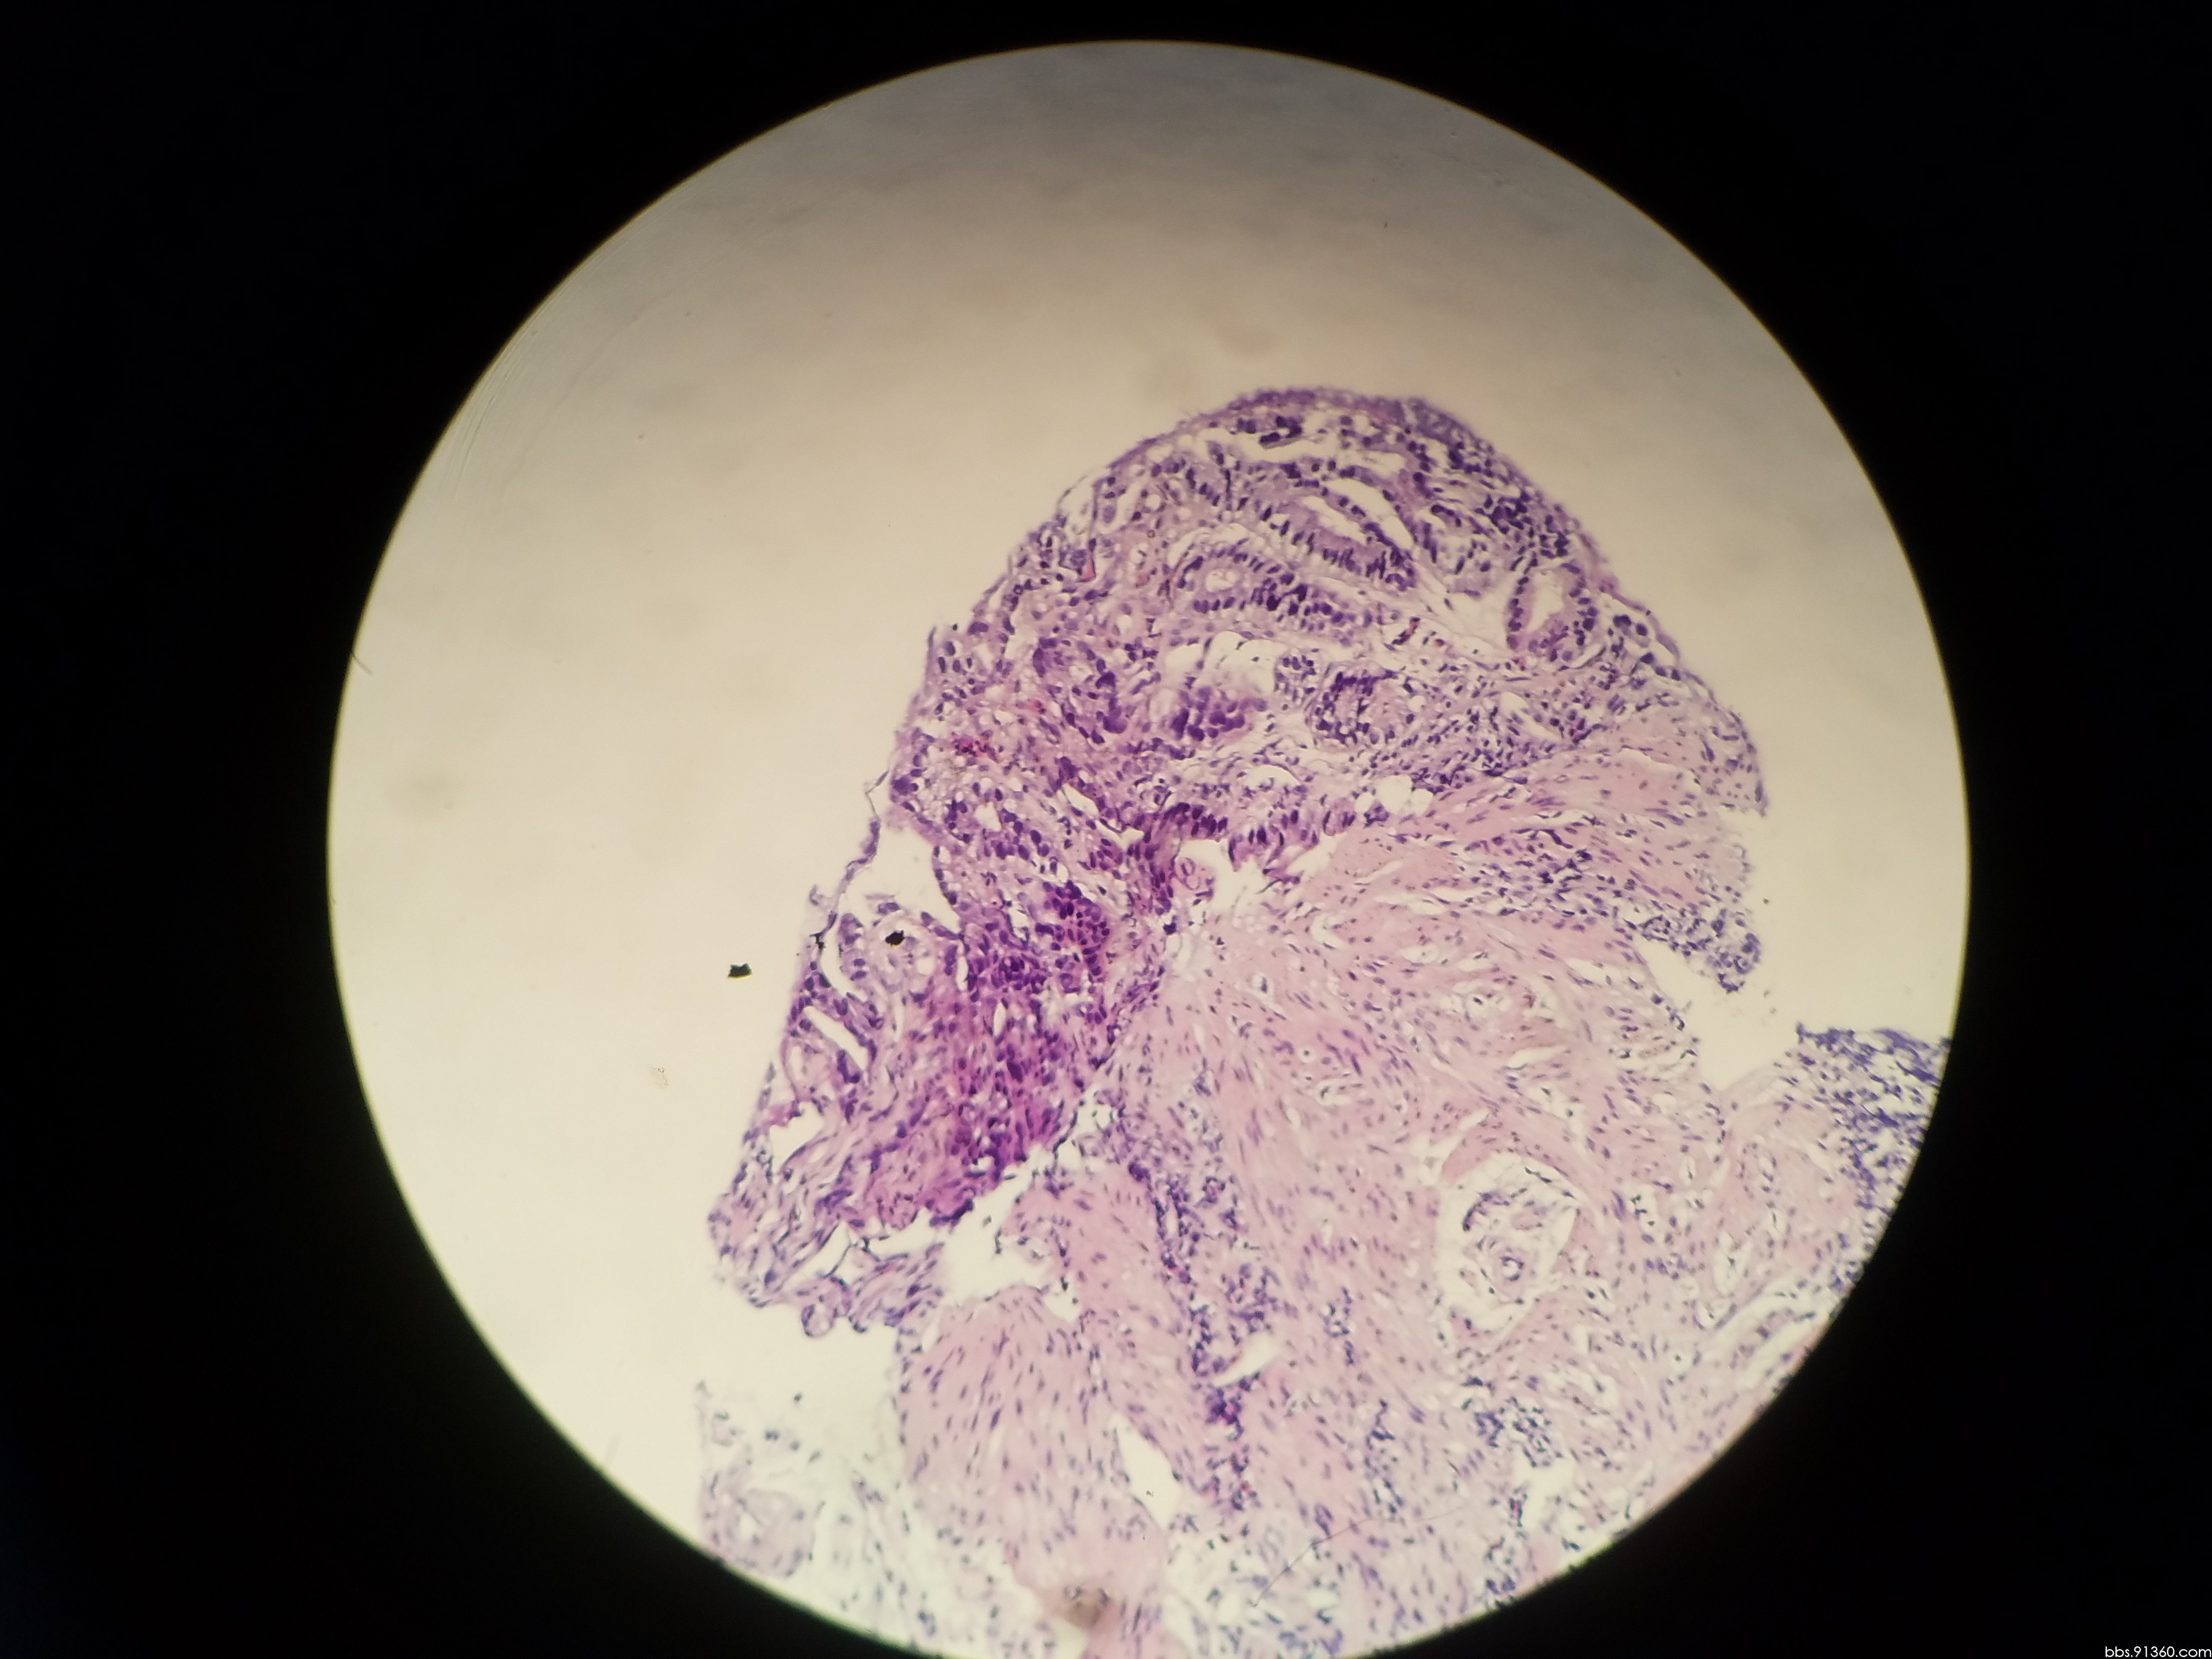

56床陈友文 胃窦腺癌 术前讨论

胃窦部黏膜组织活检镜下如图所示胃黏膜发生的有关病变的描述

胃窦部黏膜组织活检镜下如图所示胃黏膜发生的有关病变的描述错误的是

胃窦粘膜部分腺上皮呈高级别上皮内瘤变